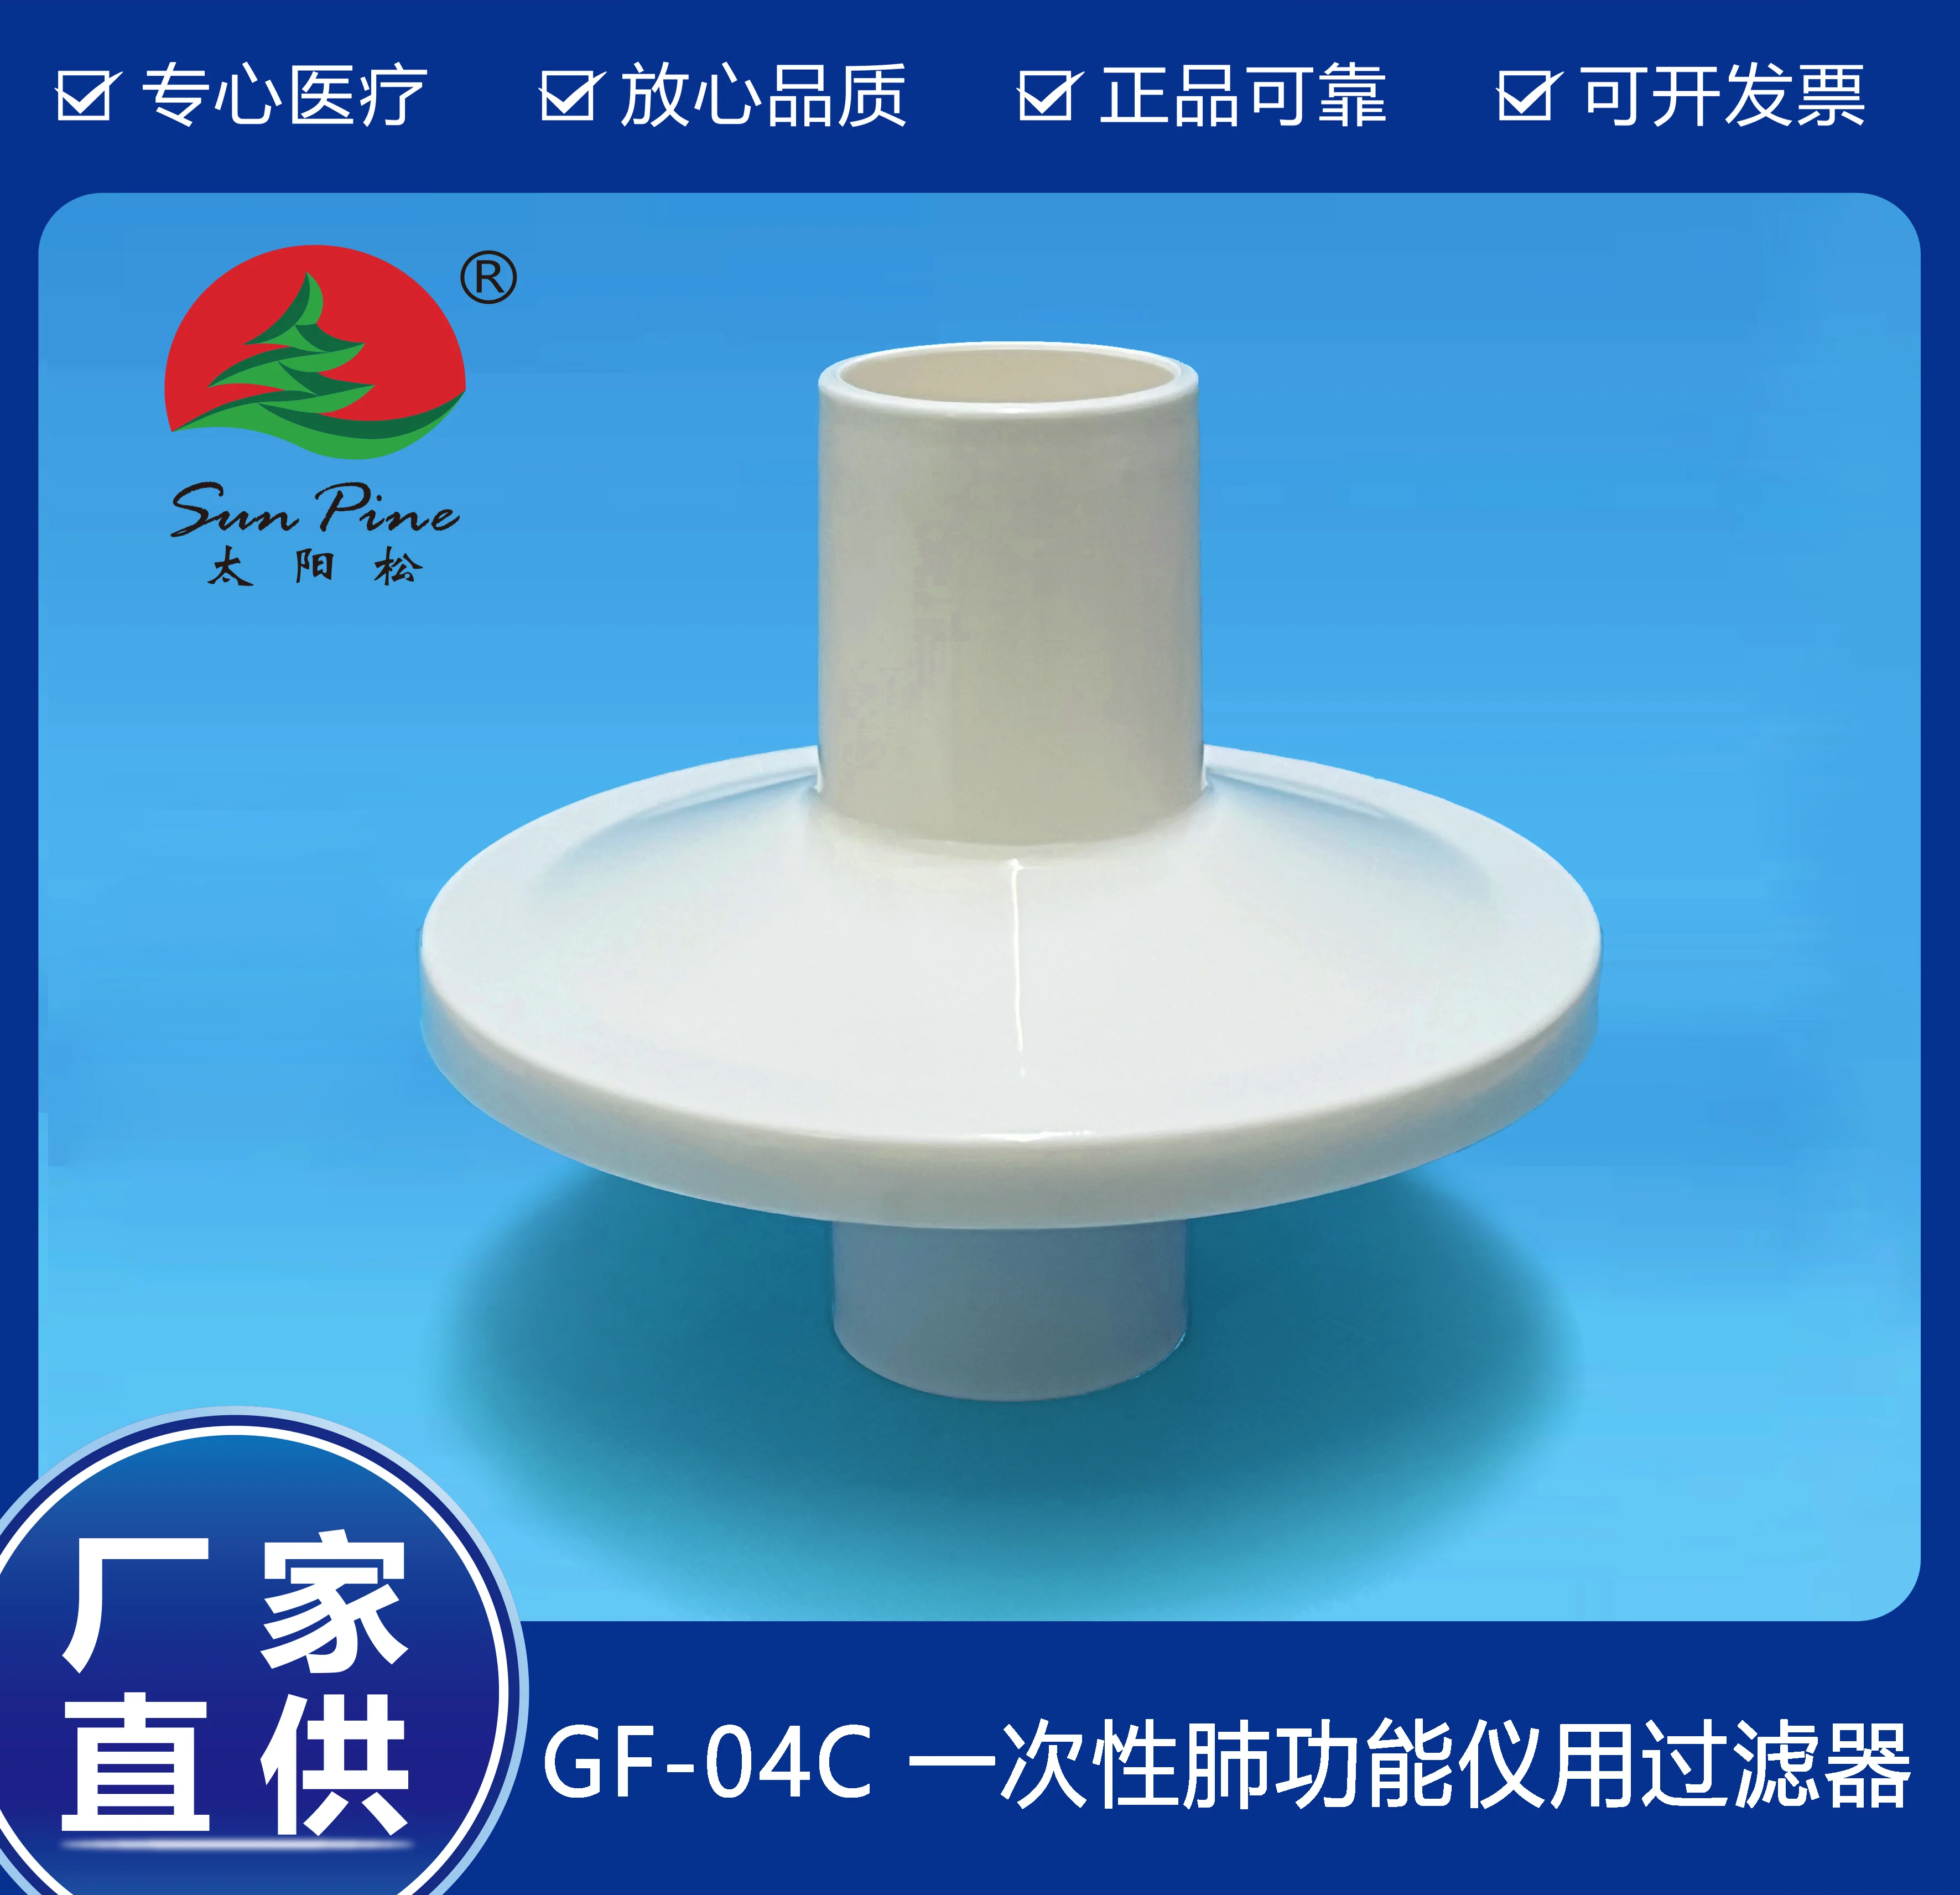

中山高榮電子科技有限公司是一家集自主研制,生產(chǎn)和銷(xiāo)售一體的高新技術(shù)醫(yī)療器械生產(chǎn)企業(yè),嚴(yán)格按照CFDA認(rèn)證,遵守國(guó)家醫(yī)療器械法規(guī)建立了完善的質(zhì)量管理體系,確保提供給客戶(hù)的醫(yī)療器械產(chǎn)品安全健康。公司擁有十萬(wàn)級(jí)、萬(wàn)級(jí)潔凈生產(chǎn)車(chē)間,環(huán)氧乙烷滅菌車(chē)間,有專(zhuān)門(mén)的物理實(shí)驗(yàn)室、理化實(shí)驗(yàn)室和微生物實(shí)驗(yàn)室以及醫(yī)電研發(fā)室、醫(yī)電生產(chǎn)車(chē)間。主要產(chǎn)品有:“太陽(yáng)松”品牌:一次性使用呼吸過(guò)濾器,一次性肺功能儀用過(guò)濾器,咬嘴;“凱華”品牌:醫(yī)用電子產(chǎn)品,肺功能檢查儀等,其中過(guò)濾器,咬嘴可匹配市場(chǎng)上各種不同品牌型號(hào)的肺功能儀使用,可以降低患者吸入或呼出顆粒性物質(zhì)的數(shù)量,防止污染儀器,大限度保障每位受測(cè)者健康安全.